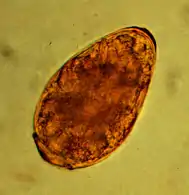

Liver flukes (opisthorchis felineus, pseudoamphistomum truncatum and metorchis bilis), which occur in cats, require a twofold change of host for their development. Water snails serve as the first intermediate host, and freshwater fish serve as the second. Cats become infected by ingesting fish. The encapsulated (encystosed) metacercariae in fish are very resistant and are safely killed only by cooking. In rare cases, infestation with liver fluke can cause intestinal inflammation with diarrhea, disturbed general condition, and liver and pancreas changes.